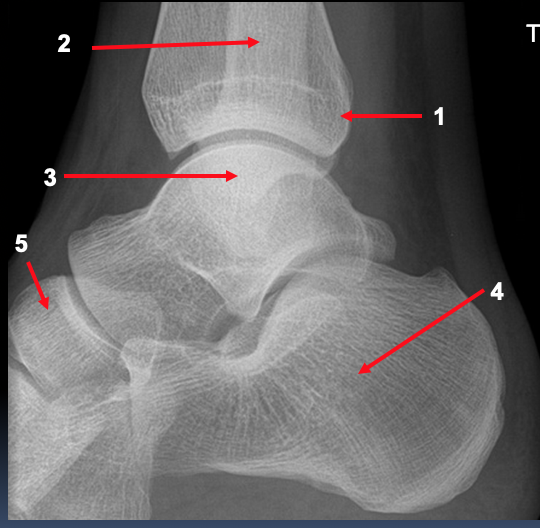

What features are shown on the lateral ankle radiograph?

Why may ankle fractures sometimes be called ‘tri-malleolar’?

if there is involvement of the posterior malleolus

this is the region of the tibia which projects distally